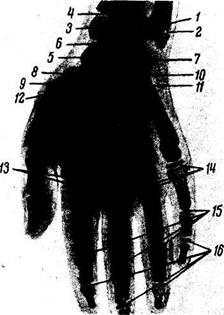

Окостенение. Кисть является наиболее удобным объектом для рентгенологического исследования развития костной системы человека. На рентгенограмме кисти новорожденного можно видеть, что окостенению подверглись только диафизы трубчатых костей, развившиеся из основных точек окостенения еще в утробной жизни (начиная со 2-го месяца). Эпифизы трубчатых костей и кости запястья находятся еще в хрящевой стадии развития и потому на рентгенограмме они не видны. В дальнейшем обнаруживаются следующие возрастные изменения скелета кисти.

I. Последовательное появление точек окостенения в костях запястья и в эпифизах трубчатых костей.

Для более легкого запоминания сроков и порядка окостенения костей запястья можно пользоваться следующим приемом: если держать перед собой рентгенограмму кисти пальцами вниз и лучевым краем направо, то порядок появления точек окостенения в костях запястья будет соответствовать ходу часовой стрелки, начиная от головчатой кости. При этом следует учесть, что срок появления костного ядра трехгранной кости соответствует числу ее граней (3 года); в дальнейшем достаточно к каждой соседней (по ходу часовой стрелки) прибавлять по одному году, чтобы получить срок окостенения. В результате порядок окостенения костей запястья будет следующим: capitatum (2 мес), hamatum (3 мес), triquetrum (3 года), lunatum (4 года), scaphofdeum (5 лет), trapezium et trapezoideum (5 и 6 лет).

Иногда на рентгенограмме ^новорожденного могут быть обнаружены костные ядра головчатой и крючковидной костей; это наряду с другими симптомами может служить признаком доношенности плода. Точки окостенения в истинных эпифизах коротких трубчатых костей появляются на 2 —3-м году. На противоположных концах этих костей иногда прослеживается самостоятельное окостенение ложных эпифизов (псевдоэпифизов). В дистальных эпифизах длинных трубчатых костей ядра окостенения появляются в лучевой кости на 1—2-м году и в локтевой — на 7 —8-м году. В сесамовидных костях точки окостенения появляются в препубертатном периоде, в гороховидной — у девочек в 7—12 лет, у мальчиков в 10—15 лет, в пястно-фаланговых I пальца — у девочек в 10—15 лет, у мальчиков в 13 — 17 лет (рис. 46, 47). Иногда сесамовидные кости развиваются из двух точек окостенения, сохраняющихся отдельно, — ossa sesamoidea bipartita.

Рис. 46. Рентгенограмма кисти мальчика 6 лет.

1 - диафиз локтевой кости; 2 — диафиз лучевой кости; 3 - эпифиз лучевой кости; 4 - точка окостенения ладьевидной кости; 5 — полу лунная кость; 6 — трехгранная кость; 7 — кость-трапеция; 8 — эпифиз I пястной кости; 9 — головчатая кость; 10 — крючковидная кость; 11 — трапециевидная кость; 12 — эпифизы II-V пястных костей; 13 — эпифизы проксимальных фаланг; 14 — эпифизы средних фаланг; 15 — эпифизы дистальных фаланг.

Рис. 47. Рентгенограмма кисти мальчика 9 лет.

1 — эпифиз локтевой кости; 2 — эпифизарный хрящ; 3 — эпифиз лучевой кости; 4 — эпифизарный хрящ; 5 — ладьевидная кость; 6 — полу лунная кость; 7 — трехгранная кость; 8 — кость-трапеция; 9 — трапециевидная кость; 10 - головчатая кость; 11 — крючковидная кость; 12 — эпифиз I пястной кости; 13 — эпифизы пястных костей; 14 — эпифизы проксимальных фаланг; /5 - эпифизы средних фаланг; 16 -эпифизы дистальных фаланг.

И. Наступление синостозов в трубчатых костях у мужчин в 19 — 23 года, у женщин в 17 — 21 год. По новейшим исследованиям, эти сроки значительно изменились в сторону более раннего возраста. Знание сроков и порядка окостенения позволяет определить заболевания эндокринных желез и других систем организма, когда наблюдается извращение окостенения.

III. Старение скелета кисти характеризуется общими признаками старения костной системы.

Из изложенного видно, что скелет кисти, состоящий из большого числа костей, претерпевает значительные возрастные изменения. Поэтому при рентгенологическом исследовании отмечается много морфологических деталей, служащих опорными пунктами для определения «костного» возраста.

Рис. 50. Рентгенограмма кисти мужчины 38 лет; ладонная проекция.

/-локтевая кость; 2 — лучевая кость; 3 - шиловидный отросток лучевой кости; 4 - дистальный луче-локтевой сустав; 5 — треугольный хрящ; б — щель лучезапястного сустава; 7 — ладьевидная кость; S — полулунная кость; 9 — трехгранная кость; /0 — гороховидная кость; 11 — кость-трапеция; 12 — трапециевидная кость; 13 - головчатая кость; 14 - крючковидная кость; 15 — пястные кости; 16 — сесамовидная кость; 17 — проксимальные фаланги; 18 — средние фаланги; 19 — дистальные фаланги.

На ладонном рентгеновском снимке кисти видны все участвующие в ее образовании кости и их детали (рис. 50). «Рентгеновские суставные щели» имеют вид полос просветлений между суставными поверхностями соответствующих костей.

«Рентгеновская щель» лучезапястного сустава в медиальной части расширена соответственно расположенному здесь суставному диску (треугольному хрящу), не задерживающему рентгеновских лучей.